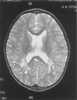

Hunter syndrome, or mucopolysaccharidosis type II (MPS II), is a rare genetic disorder in which large sugar molecules called glycosaminoglycans (or GAGs or mucopolysaccharides) build up in body tissues. It is a form of lysosomal storage disease. [Source: Wikipedia ]